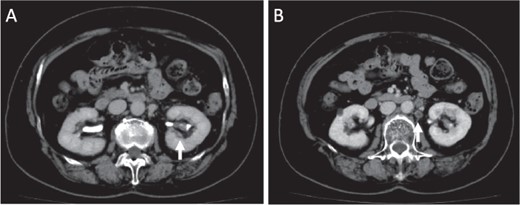

Macroscopic photographs of the tumor. Macroscopic photographs of the coronal section (A) and horizontal section (B) of the kidney. Arrows indicate the tumor.

Initially, chemotherapy using gemcitabine (1300 mg/body) plus cisplatin (94 mg/day) was started 1 month after her initial visit, resulting in progressive disease. Subsequently, methotrexate, vinblastine, adriamycin and cisplatin therapies (methotrexate, 30–39 mg/body/day; vinblastine, 3.0–3.9 mg/body/day; Adriamycin, 30–39 mg/body/kg; cisplatin, 70–92 mg/body/day) were started. A total of four courses of the therapy were performed, with no effect on the tumor size. Therefore, nephrectomy of her left kidney and dissection of the regional lymph nodes were performed 8 months after her initial visit to the hospital. As shown in Fig. 2, the tumor was observed in the lower part of the pelvis to the parenchyma of the left kidney during macroscopic examination. The tumor size was 35 × 25 × 20 mm, and the color of the tumor was whitish yellow (Fig. 2). Histologically, the tumor consisted of elongated tubular structure and spindle cells with mucinous stroma (Fig. 3A and B). The spindle cell showed enlarged nuclei and prominent nucleoli, suggesting Fuhrman grade 4 (Fig. 3C). Partially, macrophages were prominent in the tumor (Fig. 3D). Alcina blue-positive mucin was also observed in the stroma of the tumor (Fig. 4A). Although the tumor projected to the renal pelvis, the tumor was lined with normal urothelial cells.